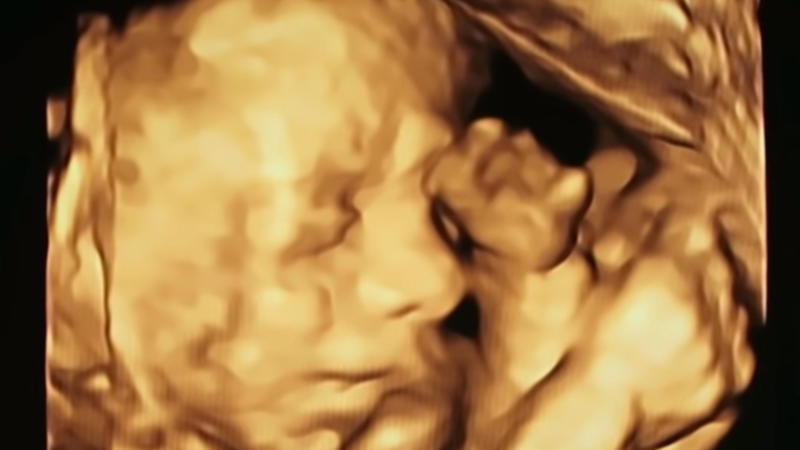

Katie was growing more and more nervous with each and every hour that was passing. Especially after reading and finding out what the future might hold for her and Angelo, but for her unborn children as well! In an interview, she admitted that they had heard tons of stories about bad things happening during pregnancies.